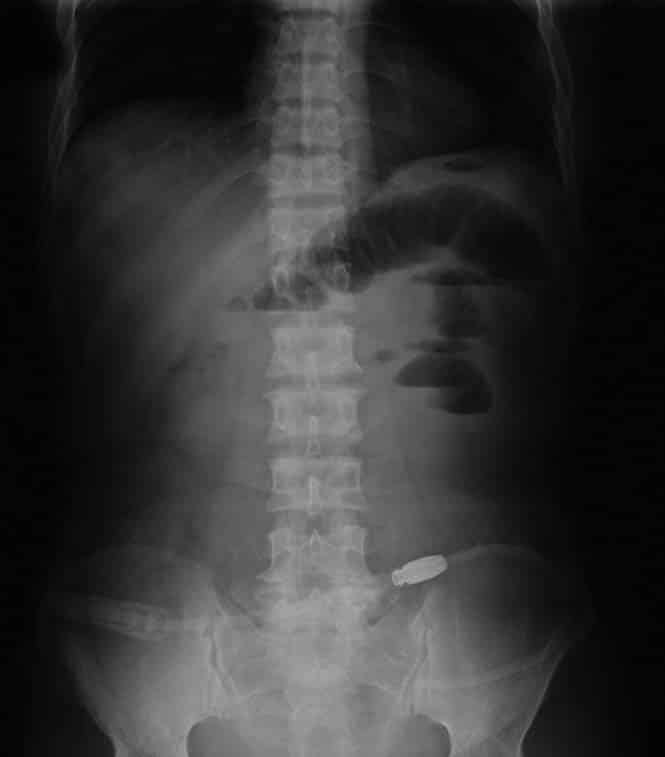

Οι κοπρανώδεις εμετοί είναι συμπτώματα αρκετών παθήσεων, καθώς η αδυναμία προώθησης του εντερικού περιεχομένου έχει εκτεταμένη παθοφυσιολογία (όπως ο αποφρακτικός ειλεός). Η μηχανική απόφραξη του εντέρου συσσωρεύει τα περιττώματα, τα οποία θα βρουν τελικά διέξοδο από τη μόνη διαθέσιμη κοιλότητα, αυτή του στόματος.

Άλλη αιτία μπορεί να είναι η άτυπη σύσπαση των γαστρικών μυών, που αναστρέφει την κανονική ροή των κοπράνων. Όπως κι αν έχει, είναι γεγονός ότι το σώμα μας μπορεί να μας αιφνιδιάσει με πάμπολλους τρόπους, άλλοτε ευχάριστα και άλλοτε εντελώς δυσάρεστα…